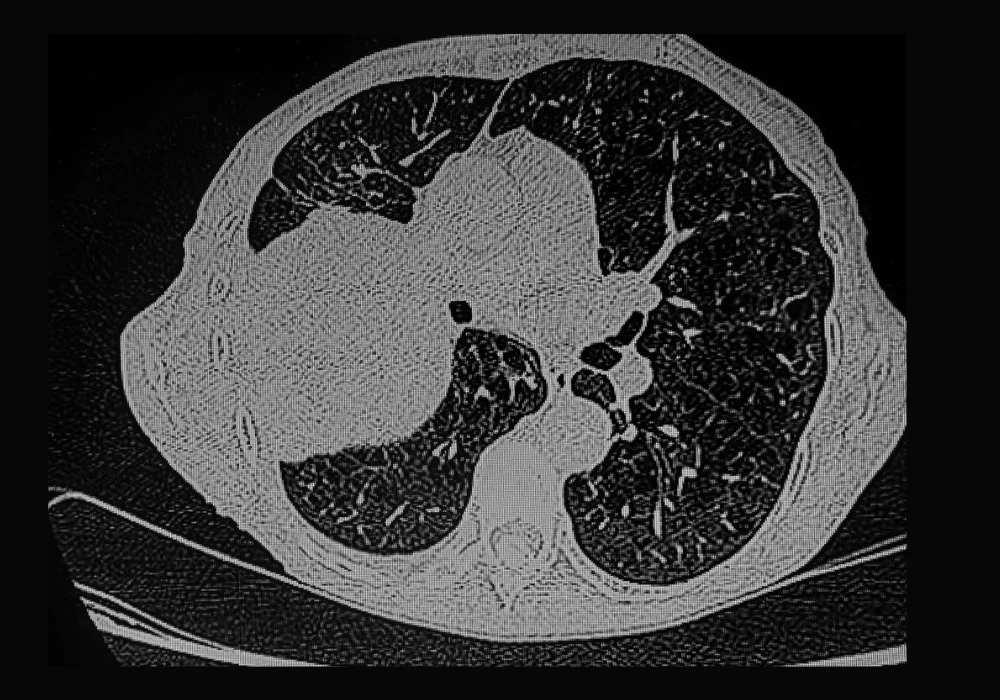

Radiomics involves extracting high-dimensional features from medical images to capture tumour heterogeneity, shape and texture. In the study in question, 826 lung adenocarcinoma patients were retrospectively analysed using thin-slice CT scans from two centres. Tumours and their surrounding regions were segmented with the aid of an automated nnUNet tool, which achieved high Dice coefficients, confirming robust performance. Radiomic features were extracted not only from tumour regions but also from concentric peritumoural zones at distances ranging from 2 to 10 millimetres.

The results highlighted that incorporating peritumoural features enhanced predictive accuracy compared to models restricted to tumour-only regions. In particular, combining the tumour region with a 2 mm peritumoural zone achieved the highest performance, with area under the curve (AUC) values of 0.843 and 0.803 in internal and external validations. Shapley value analysis identified key radiomic parameters such as percentile intensity measures and texture correlations as influential predictors. These findings emphasise that biological changes in surrounding tissues provide critical signals that can support accurate classification of EGFR status.

Consistently, 3D networks outperformed 2D and 2.5D models across most regions, reflecting their ability to capture richer structural details. For the combined tumour and 2 mm peritumoural zone, the 3D deep learning model achieved an AUC of 0.814 in external validation, the highest among all deep learning models tested. Visualisation using Grad-CAM saliency maps confirmed that predictive attention extended beyond tumour borders into surrounding tissue, supporting the inclusion of peritumoural regions.